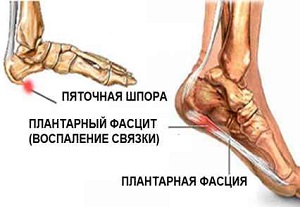

Сильные резкие боли в пятке обычно свидетельствуют о возникновении плантарного фасциита, который в народе известен как пяточная шпора. Опасность заболевания заключается в утрате человеком способности опираться на больную ногу, что приводит к временной нетрудоспособности и ухудшению качества жизни. Причины возникновения пяточной шпоры и способы ее лечения рассмотрим ниже.

Во время ходьбы, бега и в положении стоя стопа часто испытывает чрезмерную нагрузку, в результате которой происходят микроповреждения и надрывы фасций. Это именно то, от чего возникает пяточная шпора.

При постоянных микротравмах фасции не успевают восстанавливаться, в результате ткани воспаляются и становятся болезненными, а их заживление сопровождается образованием рубца и костными разрастаниями.

Название выбрано не случайно – на рентгене отображается костное уплотнение на пятке в виде шпоры.

Чаще всего патология возникает на фоне плоскостопия и артроза голеностопа, так как на развитие фасциита оказывает влияние неправильное распределение нагрузки на голеностопный сустав. Остальные причины заболевания рассмотрим ниже.